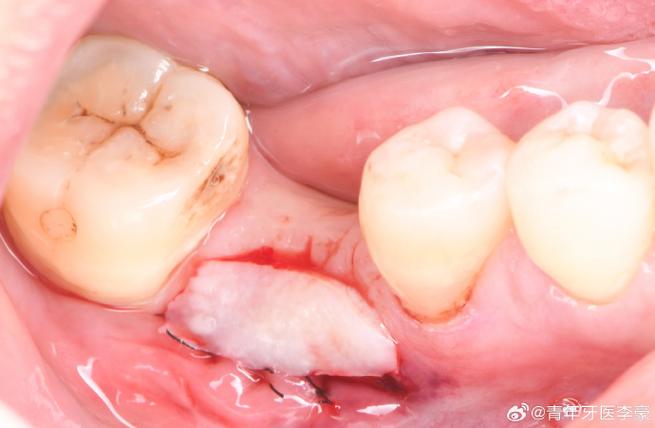

📌 4. 为什么骨粉会漏出来?

- 缝合不严密或脱落: 这是最常见的原因之一,缝合线可能松了,或者线结脱落导致缝隙。

- 过早用力或负压: 术后过早用力漱口、吸管喝水、吸烟、吐口水等,导致血凝块和骨粉被吸出。

- 伤口裂开: 由于局部感染、组织愈合不良、或意外碰撞导致伤口裂开。

- 骨量不足: 骨粉流失最大的风险是导致植骨区域的骨量不足以安全、稳定地植入种植体,或者影响种植体的长期稳定性(骨结合)。

- 感染风险增加: 骨粉暴露在口腔环境中,成为细菌滋生的温床,容易引发局部感染(骨髓炎),这会严重破坏骨组织,导致植骨失败。